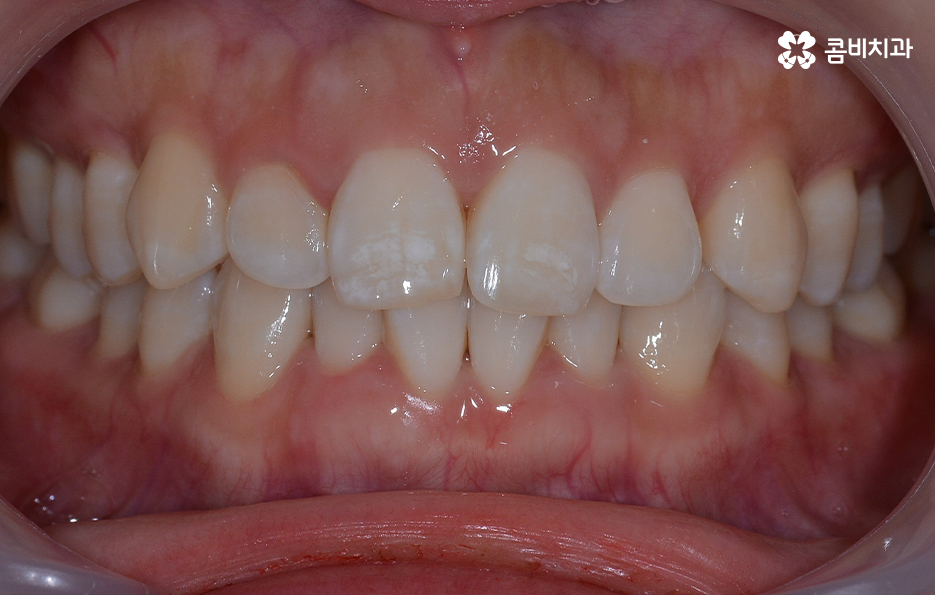

출처 아카이브 열기과거에는 주걱턱, 돌출입과 같은 부정교합이거나 덧니가 심한 경우에 치아교정을 하는 분들이 많았다면 요즘은 비교적 치열의 불규칙함이 심하지 않거나 치아가 약간 벌어진 경우에도 보다 가지런한 치열과 외모적 개선을 위해 치아교정을 알아보는 분들이 늘고 있는데요

특히 30,40대 이후에 교정하는 분들이 늘고 있는 추세인데 치아가 삐뚤빼뚤하거나 치아 사이가 벌어져서 발생할 수 있는 구강질환을 예방하는 목적과 치아가 돌출되거나 삐뚤하여 교정을 통해 외모적인 개선을 목적으로 하는 경우와 같이 다양한 목적으로 치료를 알아보실 거예요.

교정 치료는 크게 발치와 비발치치아교정으로 나뉠 수 있는데 비발치치아교정의 경우에는 아무래도 치아가 움직이는 양도 적고 그에 따라 교정 기간도 짧은 편에 해당되고 있어요.

반면에 비발치치아교정으로도 충분히 좋은 결과를 얻을 수 있는 경우도 있을텐데 이러한 치료 과정 상의 특징과 장단점을 고려하여 자신의 치료 계획을 경험 많고 숙련된 교정 전문의와 잘 상의하실 필요가 있어요

단순히 비발치치아교정이 발치를 안해도 되니 무조건 좋다고 판단하기 보다는 각 개인의 치료 목적과 구강 및 골격, 얼굴형의 상태를 종합적으로 정밀 검진하여 자신에게 적합한 치료 계획을 잘 세우는 것이 중요하다고 강조드리고 있어요